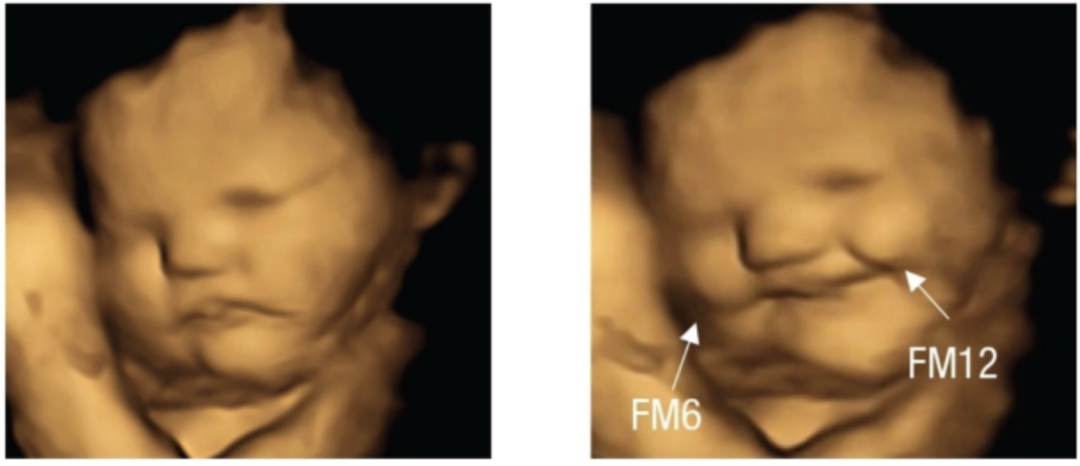

2022 年 9 月,一项发表在 Psychological Science 上的研究首次拍到了胎儿对母亲所吃食物的味道的面部反应。

研究人员把 100 名怀孕 32~36 周的孕妇分为两组,一组服用羽衣甘蓝粉,一组服用胡萝卜粉。然后 20 分钟后对孕妇腹部进行 4D 超声波扫描,惊奇地发现:

面对带「苦味的羽衣甘蓝」,胎儿更多给予的是一副哭脸;而对「带甜味的胡萝卜」,胎儿则更多地报以「笑脸」。

左为正常情况下胎儿的表情,右为羽衣甘蓝组宝宝的哭脸表情。

左为正常情况下胎儿的表情,右为胡萝卜组宝宝的笑脸表情。